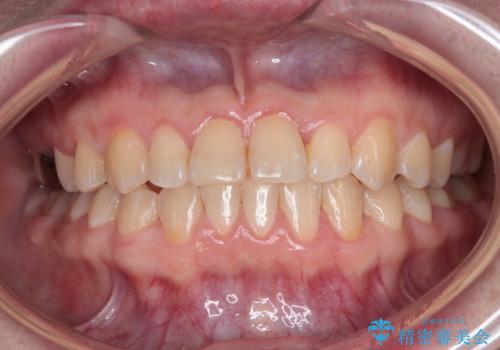

外側に飛び出した歯 インビザラインによる矯正治療

- 外に飛び出した側方の歯と、前歯のデコボコを気にして来院された患者様です。

IPR(歯と歯の間を削る)によってデコボコが解消するように設計し、インビザラインにより治療を行うこととしました。

治療途中で1年半以上通院されない時期があったため、後戻りが生じたことで治療期間が長くなってしまいました。

親知らずを抜去したことで、下顎のデコボコがきれいに解消されました。